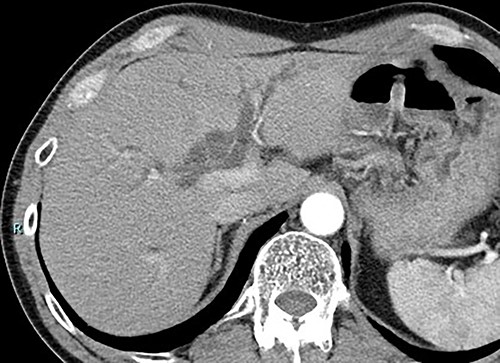

Contrast-enhanced computed tomography (CT) revealed wall thickening and stricture of the distal common bile duct (CBD) (Fig. 1). Dilation of both the intrahepatic bile ducts and the common hepatic duct was also observed (Fig. 2). No lymph node or distant metastases were observed. Endoscopic retrograde cholangiopancreatography revealed irregular stenosis in the distal CBD (Fig. 3). Thereafter, biliary drainage and brush cytology were performed, and an adenocarcinoma was detected.

CT scan showed wall thickness and stenosis of the distal CBD (arrow).